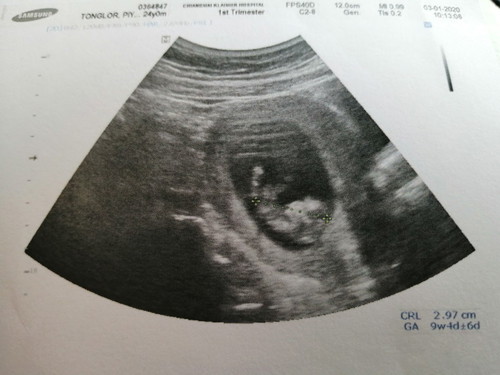

ฝากครรภ์ ครั้งแรก 03/01/2563

ตอนนี้น้อง อายุครรภ์ ได้ 10 สัปดาห์แล้ว ยาว 2.97 cm. แม่กับพ่อได้เห็นลูกครั้งแรก น้ำตาจะไหล รักนะตัวน้อย